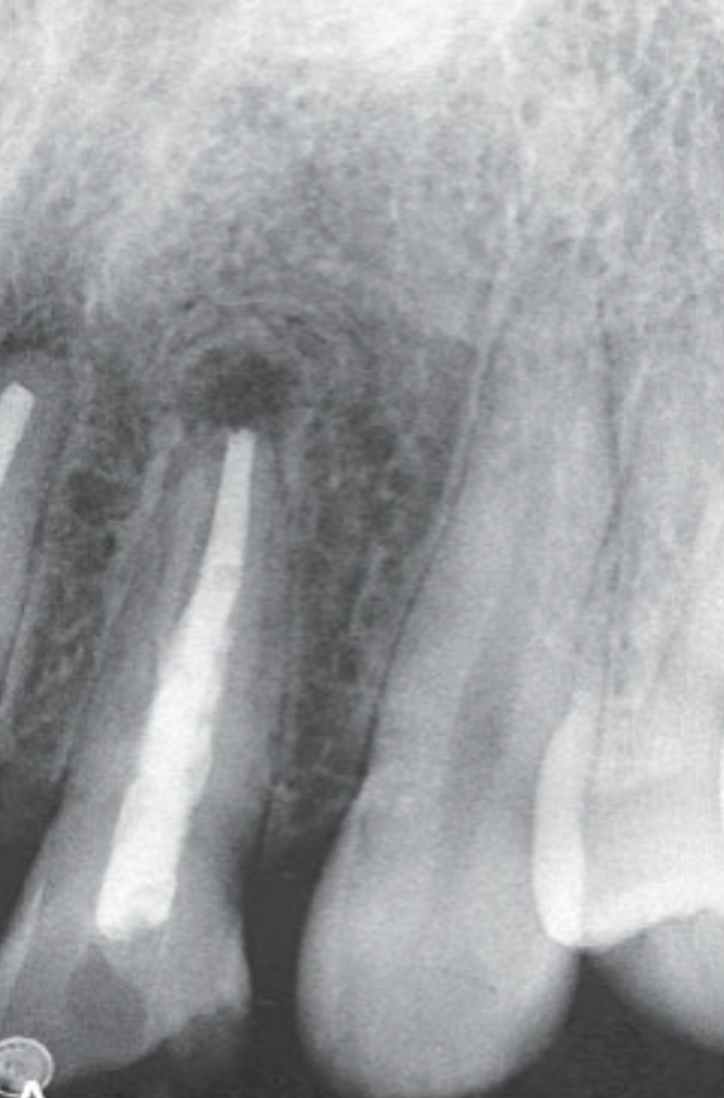

post-treatment changes

radiolucent areas may persist after successful orthograde or retrograde endodontics

central radiolucency may represent healing connective tissue

periophery may show granular bone or radiating trabeculae → “rolled border” or doughnut/fibrous scar pattern